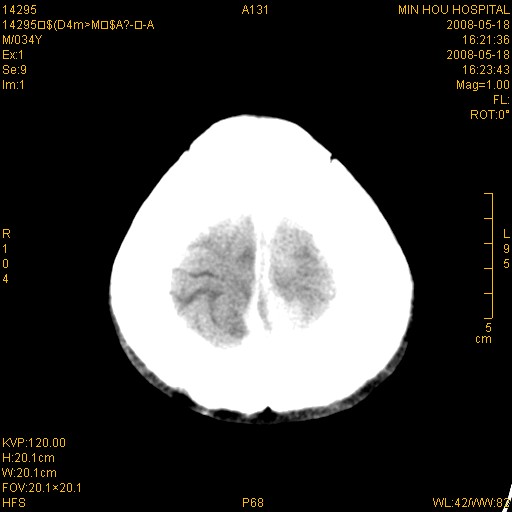

标题: CT13617:双顶叶白质水肿伴大脑镰小脑幕广泛钙化 [打印本页]

标题: CT13617:双顶叶白质水肿伴大脑镰小脑幕广泛钙化

多年前频发抽搐生活不能自理,行ct平扫,诊断为双顶叶占位。因贫未能进一步检查。

目前偶有抽搐,能从事油漆工作。原片未能获取。

双侧侧脑室后脚旁对称性低密度影,符合肾上腺白质营养不良(成人型)改变    小脑幕及大脑廉钙化  可考虑为生理性

支持:1、肾上腺白质营养不良.2、小脑幕、大脑镰广泛钙化。3、建议进一步检查。

硬脑膜钙化是主因,双侧顶叶白质密度减低是可能由于静脉路回流受阻所致。